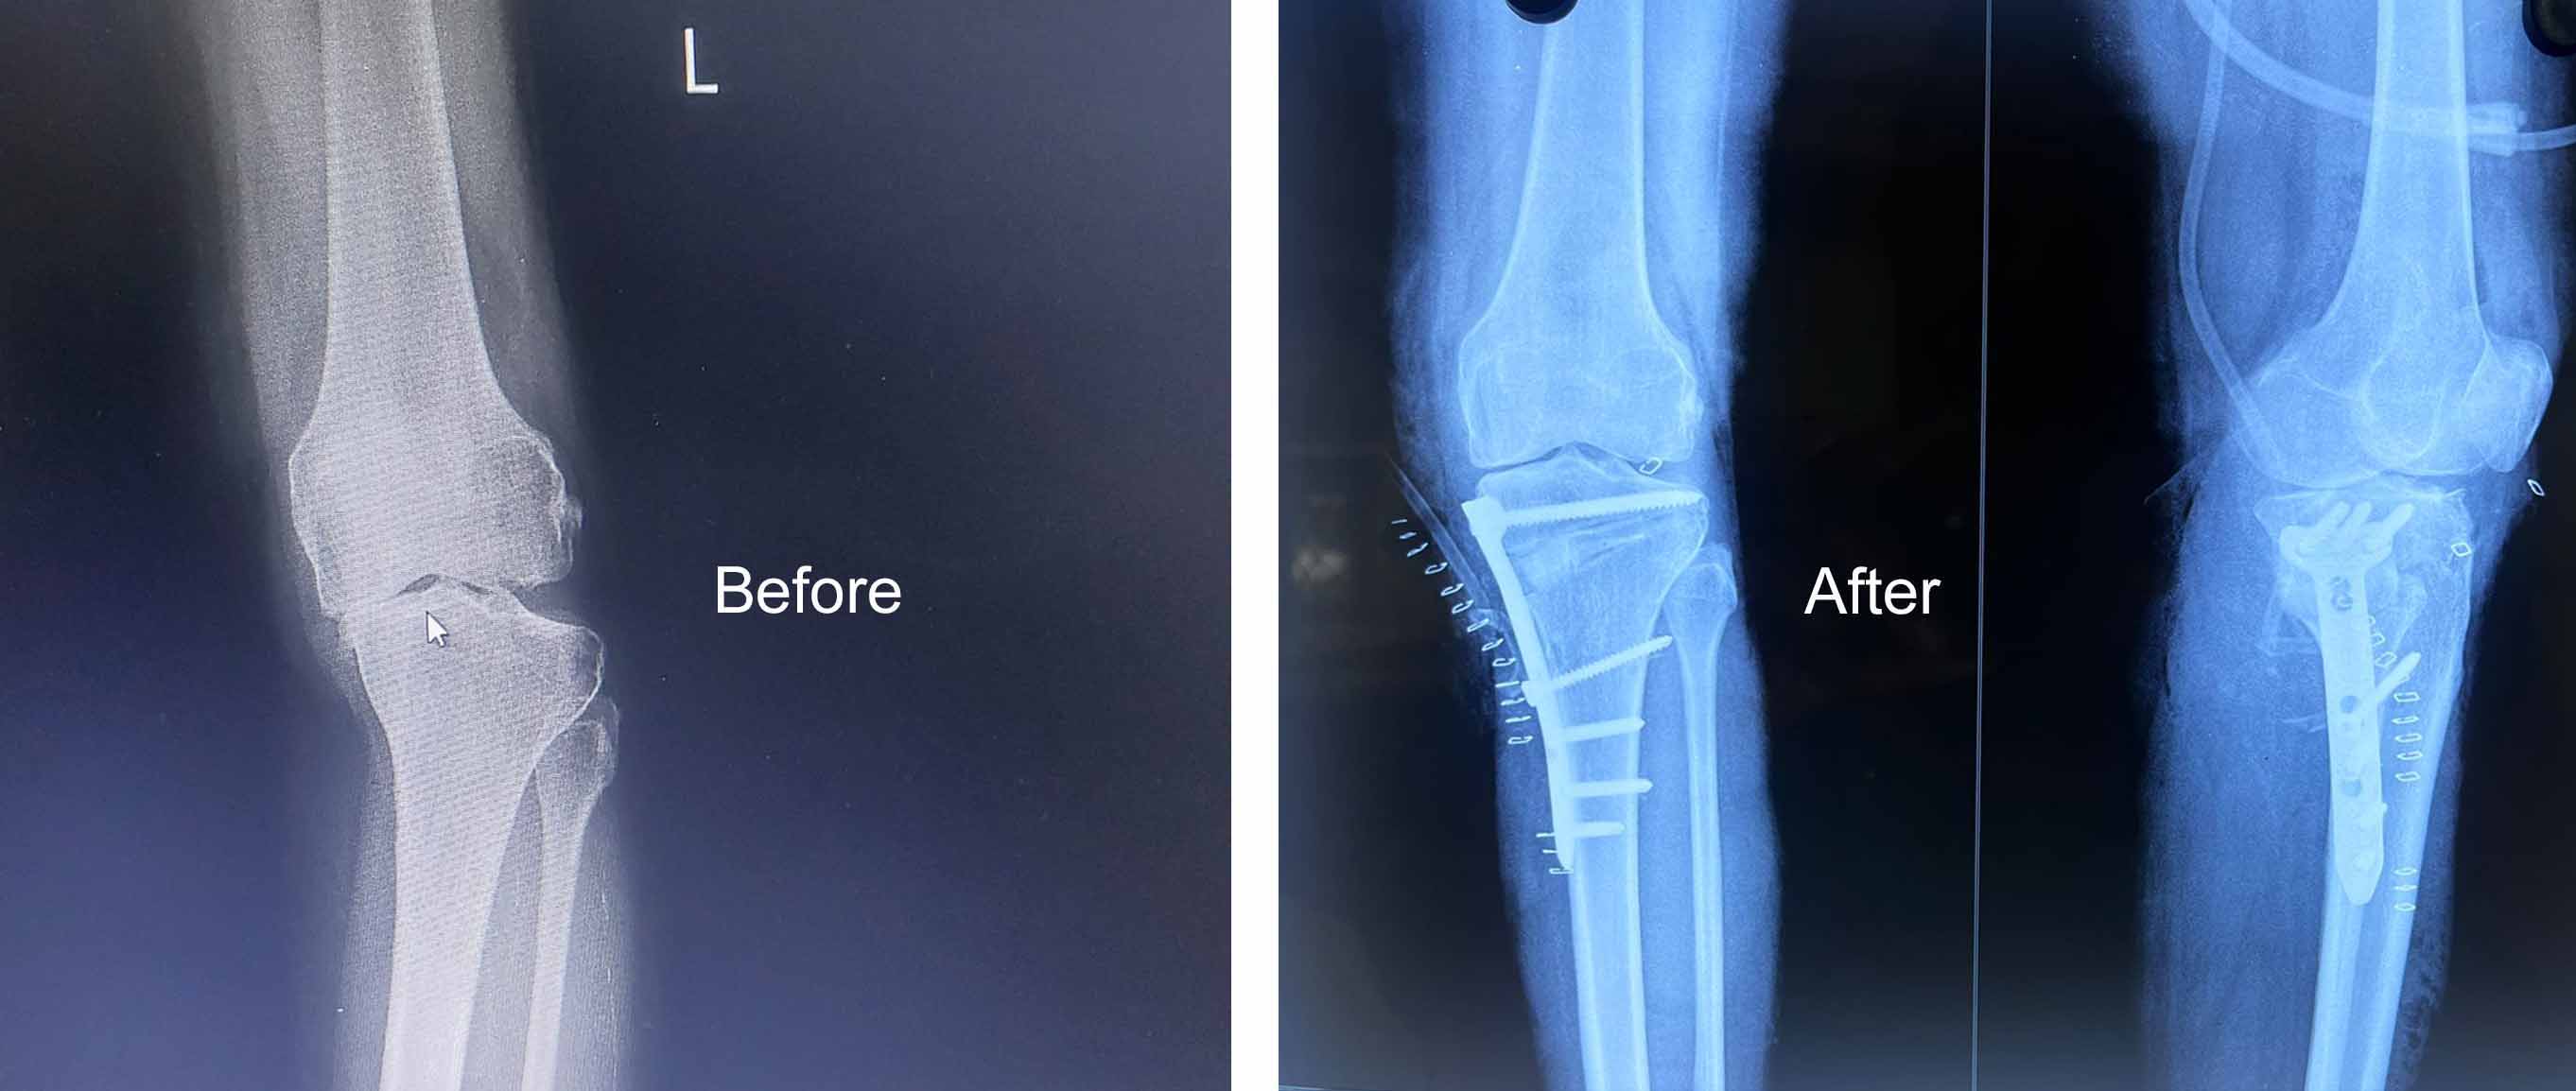

Medical Gallery

Orthopedic Care